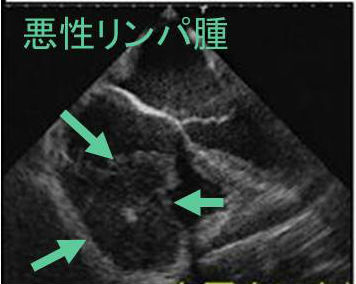

転移性心臓腫瘍は、悪性腫瘍剖検例の4.7~15.0%と意外と多い。原発巣は肺癌、乳癌、血液癌、悪性黒色腫が多く、甲状腺癌による転移性心臓腫瘍は少ない。(J Clin Pathol. 2007 Jan;60(1):27-34.)

甲状腺癌による転移性心臓腫瘍は、甲状腺未分化癌が最も多く、次いで甲状腺濾胞癌です。